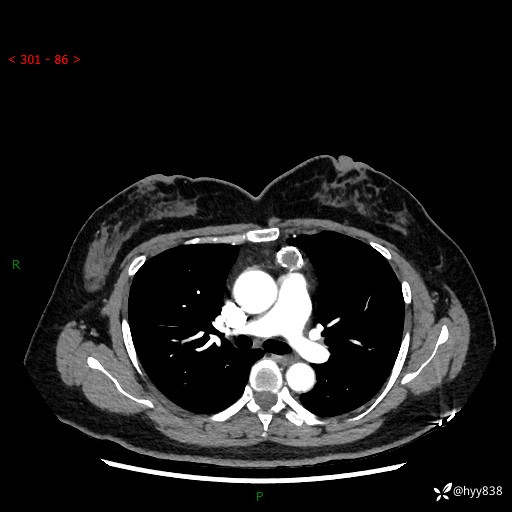

中年女性,检查发现纵隔占位3月余。圆圆的肿物,周围环绕一圈钙化---结果公布~

主诉:检查发现纵隔占位3月余。

现病史:患者于3月前体检行胸部CT检查发现纵隔占位,患者平素无明显咳嗽咳痰,无心慌、胸闷、胸痛、呼吸困难、低热、盗汗,无头痛、头晕,无腹痛、腹胀等不适。现患者欲求进一步治疗,遂来我院就诊,以“纵隔占位”收入我科。 患者自起病以来,精神可,睡眠可,饮食可,大小便正常,体重无明显改变。

胸部CT平扫+增强